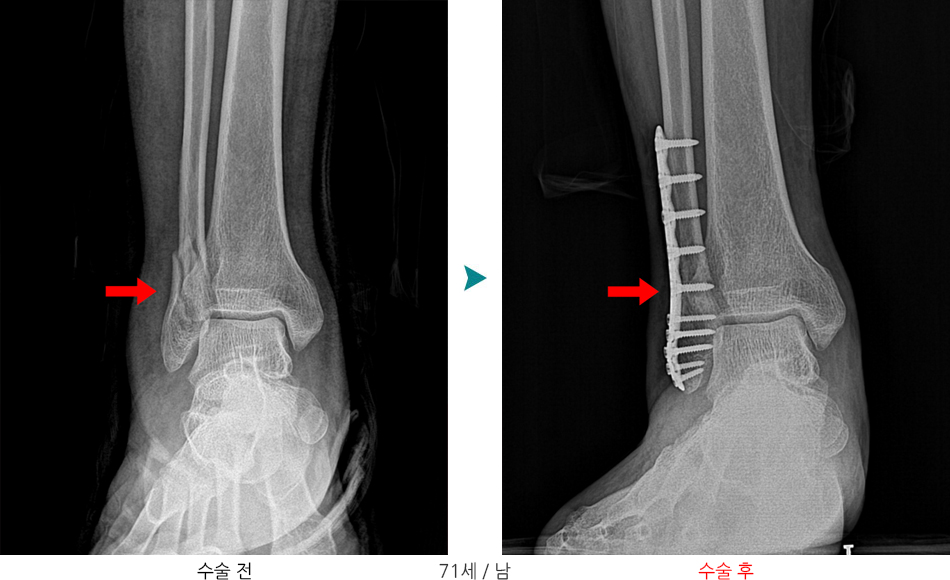

"발목 복사뼈 골절(Malleolar fracture)"

발목 복사뼈 골절(Malleolar fracture)은 발목 관절을 이루는 경골(tibia)과 비골(fibula)의 원위부(아래쪽 끝)에 발생하는 골절로, 매우 흔한 하지 외상 중 하나입니다.

• X-ray 기본 / 필요 시 CT(관절면 확인), MR(인대 확인)

불안정성 골절, 전위가 큰 경우

- 금속판(plate), 나사(screw) 고정

외측복사 골절, 금속판/금속나사를 이용한 내고정술